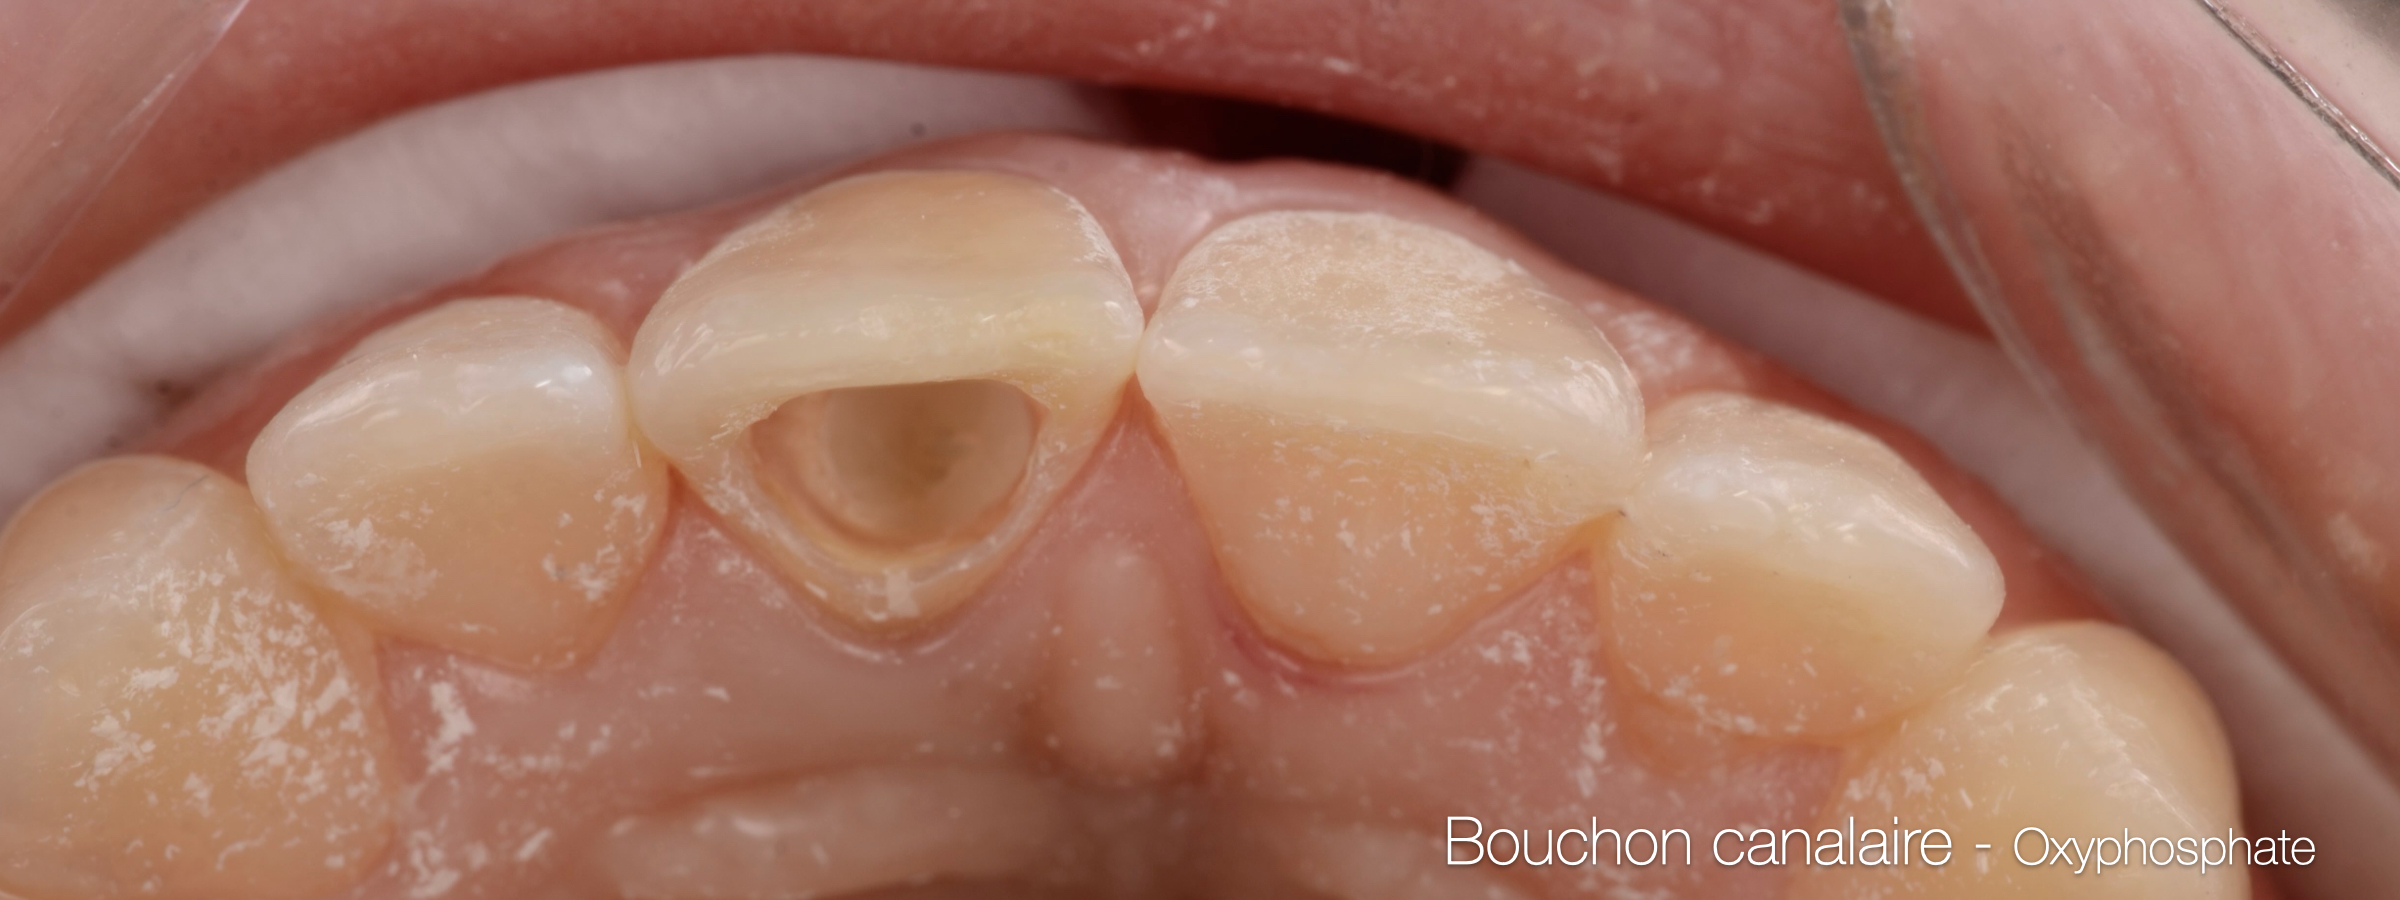

Fig. 01 : situation initiale.

Fig. 02 : situation initiale.

Fig. 03 : situation initiale.

Fig. 05 : vue palatine montrant une perte d’étanchéité coronaire.

Fig. 09 : bouchon canalaire.